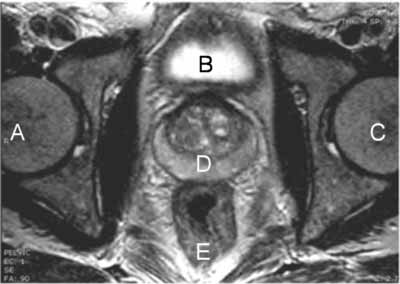

MRI of Prostate

- Find the prostate. Hint, look for the crescent shaped structure as seen in the transverse view of the prostate in the MRI image above.